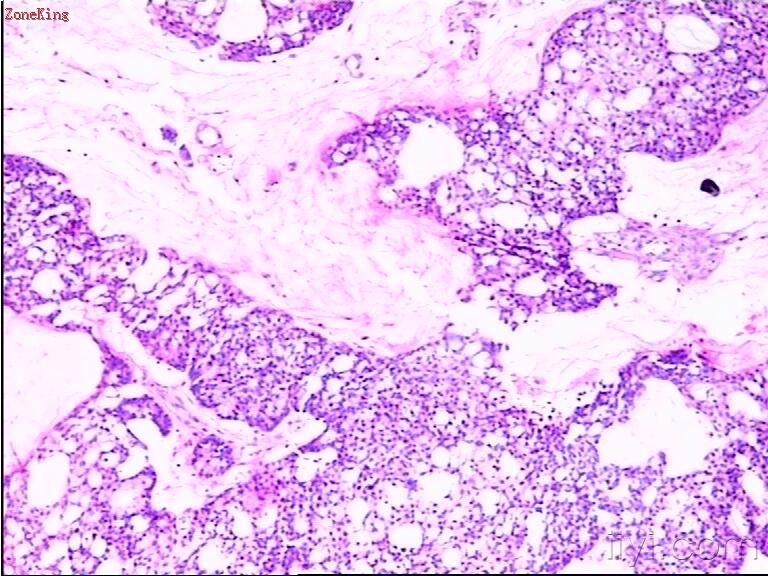

睾丸肿物,30岁,肿物位于睾丸白膜内,紧靠白膜,切面呈胶冻状。

部分区被覆上皮为粘液性上皮,考虑为粘液性囊腺癌;

30岁男子,睾丸肿块,有以下考虑:1. NSGCT2. 睾丸类癌。可以作为NSGCT的一个成分,也可以是来源于自身内分泌细胞的一个原发肿瘤或者是来自胃肠道肿瘤的一个转移瘤。 建议进一步做相关免疫组化(PLAP、AFP、HPL、NSE、PSA、β-HCG、CD30、EMA等待)或全面检查确诊。